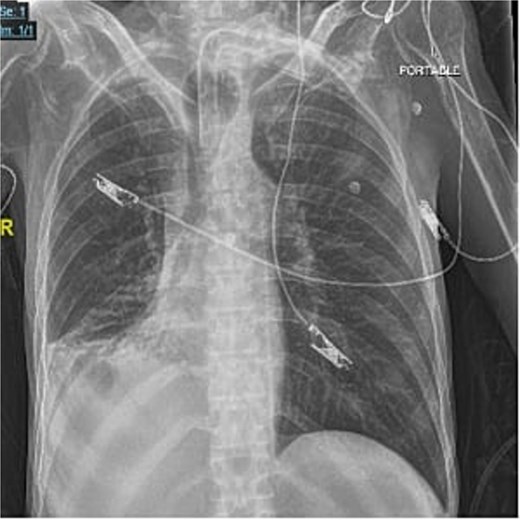

A 40-year-old male who is known to have amyotrophic lateral sclerosis was admitted to the intensive care unit for ventilatory support. He underwent surgical tracheostomy for long-term mechanical ventilation dependence, a double-lumen tracheostomy tube with an internal diameter of 8 mm and a maximum cuff pressure of 25.4 mm was inserted, post-operative chest X-ray confirmed tube placement (Fig. 1). Six months later, the otolaryngologist on-call was consulted regarding ventilation leak that was evident in the ventilator. Flexible endoscopy through the stoma revealed a significantly dilated trachea with a posterior groove. The tube was changed to size 7 with an extended distal length of 49 mm to bypass the dilated segment. A temporary improvement was noted; however, the leak was noted again, with an inspiratory tidal volume of 800, and an expiratory volume of 135, the cuff pressure was gradually elevated to overcome the leak reaching a maximum of 40 mmHg, with the cuff seen over-inflated in routine supine chest X-ray (Fig. 2). Multiple tube obstruction events happened later, which required rigid bronchoscopy examination under general anesthesia to assess and relieve the obstruction. Intraoperative examination revealed that the obstruction was caused by a large dry blood clot, withdrawal of the tube to examine the trachea further revealed a large posterior tracheal wall defect with exposed thoracic vertebrae. The patient underwent a subsequent contrast-enhanced computed tomography scan (CECT) of the neck and chest which confirmed the intraoperative findings (Fig. 3). The leak was not improving by increasing cuff pressure, consequently, the decision was made to use an armored endotracheal tube size 8 at a lip level of 13 to bypass the defect. This has slightly improved the oxygenation and ventilation of the patient, but it did not eliminate the leak. The general poor health of the patient along with his do-not-resuscitate (DNR) status has led to deterring the decision of surgical tracheal wall repair. The patient was further diagnosed with sepsis due to multiple infection sources including his long-term suprapubic urinary catheter, he eventually had a cardiopulmonary collapse a few weeks later and passed away.

Post-operative frontal portable chest radiograph showing a tracheostomy tube in position above the carina.